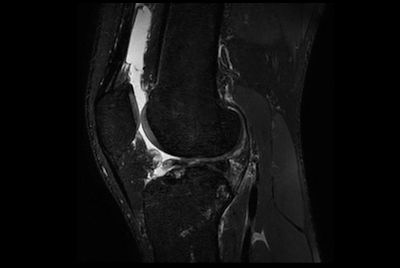

SmartSpeed Traumatic Knee imaging

-

SmartSpeed 2 min Knee imaging

-